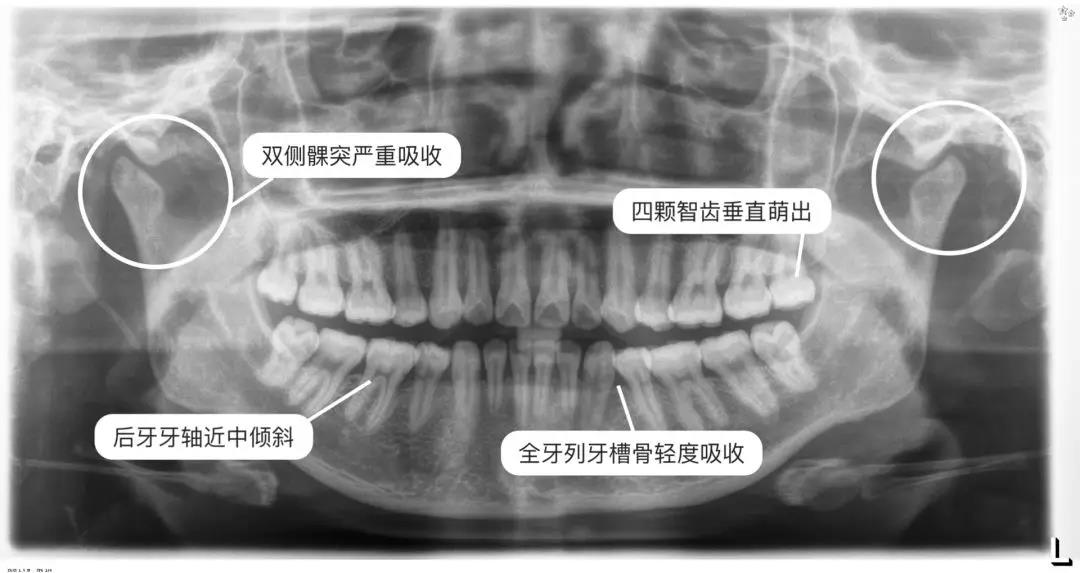

拍片

一般在面診時

醫師通常會讓你拍兩張X光片

一張全景一張側位

通過這兩張片子

醫師能夠對你的牙齒、牙根、牙槽骨、頜骨

甚至關節等進行判斷、數據分析

看到一些肉眼無法發現的問題